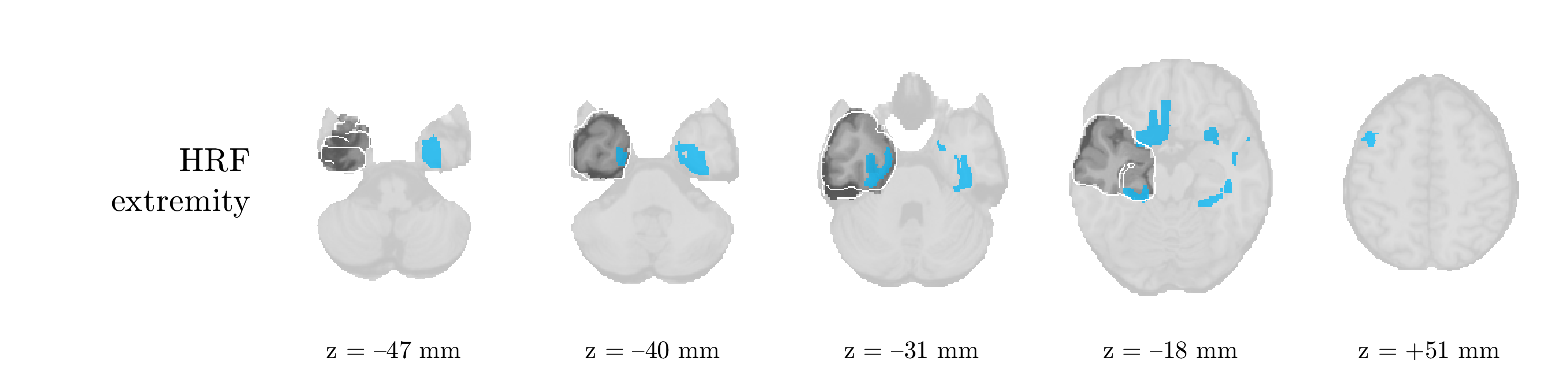

We analyze the solution with sources, and show the results in Figure 3 and 4. As for patient 1, we found a source which is strongly correlated to the MWF envelope, and which had a mostly low-frequency behavior characteristic for spikes. The topography is mostly uninformative, and does not clearly correspond to the patient’s clinical data. The third source is mostly present at both sides of the head, is very sparsely active in time, and has a high-frequency content: this is most likely an artifact due to the neck muscles. Again, there is one of the highest-entropy HRFs which belongs to a ROI in the IOZ. Now, the waveform is clearly resolved from the other HRFs, through the strong initial dip (before 0 seconds). Such a dip is sometimes observed in HRFs, but its underlying physiological mechanism is not yet fully understood. It is possible that this dip reflects altered vascular autoregulation near the IOZ (cfr. the explanation in the Section 1 of the main text), or a rapid depletion in oxygen due to IED generation (before the IED becomes visible on the EEG). Figure 4 furthermore shows that the IED-related component is significantly active in parts of the IOZ, and deactive in others. As mentioned earlier, this deactivation may or may not be due to errors in sign correction. Interestingly, the ROI with the high alteration in neurovascular coupling is distinct from both the activated and deactivated ROIs.